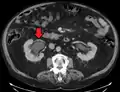

Left sided hydronephrosis in a person with an atrophic right kidney. Stent is also present (image below).

Left sided hydronephrosis, coronal view. Stent is also present.